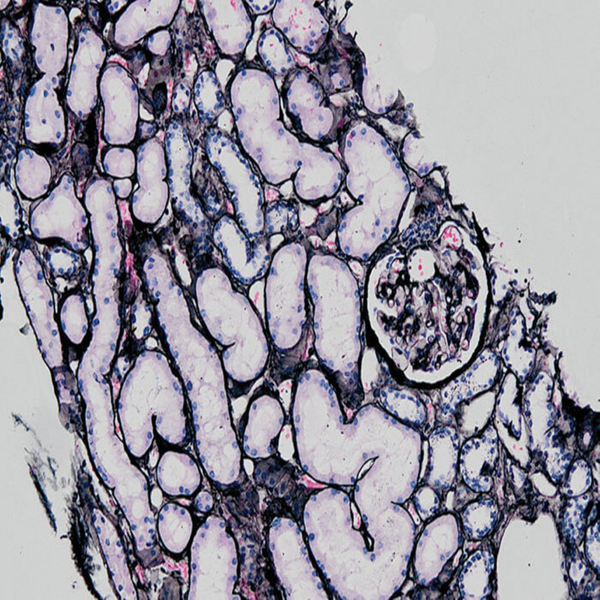

- Preparation of paraffin and frozen tissue sections in different sizes

- General and specialized tissue and cell staining

- Preparation of sections from chemical and natural tissue scaffolds

- Examination of cell placement on tissue scaffolds with SEM microscopy

Histological methods includes sample processing in the pathology laboratory, preparation of the slide and its examination under a microscope, sample fixation, molding, microtome cutting, staining and assembly of the slides.

On the other hand, in cutting-edge sciences such as tissue engineering, the use of up-to-date techniques for section preparation and cell tracking and engineered tissue structure has contributed significantly to the development of new studies.